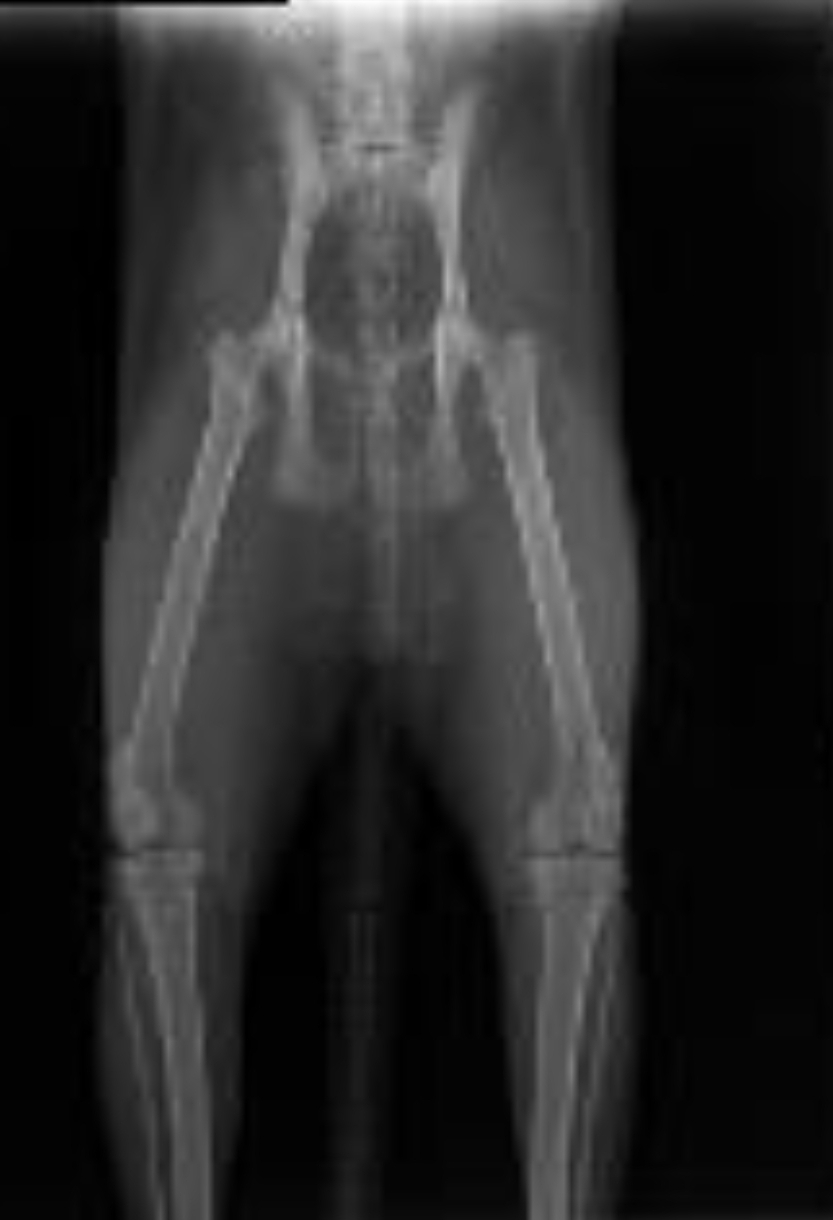

Lynn HD screen 👌

Afbeelding – 161,3 KB

148 downloads

Download